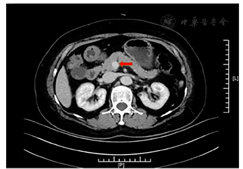

体格检查:身高165 cm,体重73 kg,腰围96 cm,臀围113 cm,体重指数26.8 kg/m2,血压130/70 mmHg(1 mmHg=0.133 kPa)。皮肤无黄染,头颅无畸形;胸廓无畸形,无压痛,触觉语颤对称,叩诊清音;腹软,无压痛,肝脾肋下未及,肝肾区无叩击痛。无胫前斑,针刺觉、音叉震动觉、触痛温度双侧正常。膝反射、踝反射双侧正常,双侧足背动脉搏动正常。无足部溃疡。辅助检查:空腹血糖2.70 mmol/L、餐后2 h血糖10.80 mmol/L、HbA1C 6.50%;游离三碘甲状腺原氨酸(FT3)4.74 pmol/L(参考范围3.10~6.80 pmol/L,下同)、游离甲状腺素(FT4)17.87 pmol/L(12.00~22.00 pmol/L)、促甲状腺激素(TSH)1.79 mU/L(0.27~4.20 mU/L)、甲状腺球蛋白抗体<10 U/ml(0~115.0 U/ml),甲状腺过氧化物酶抗体9.64 U/ml(0~35.0 U/ml)。皮质醇0∶00 am为25.27 μg/dl(7∶00~10∶00 am为6.2~19.4 μg/dl,4∶00~8∶00 pm为2.3~11.9 μg/dl),胰岛素抗体(-)。甲状腺B超提示左侧甲状腺结节,肾上腺超声、垂体核磁共振成像(MRI)增强未见明显异常。胰腺动态电子计算机断层扫描(CT)增强提示胰头钩突区见小结节影,直径约12 mm,边界清,增强后见明显持续性强化,结合临床考虑诊断为"胰岛素瘤"(图1)。术前动态血糖监测(CGMS)提示午餐、晚餐后有低血糖发生,最低3.7 mmol/L(图2A)。

注:红色箭头所指,胰头钩突区小结节影